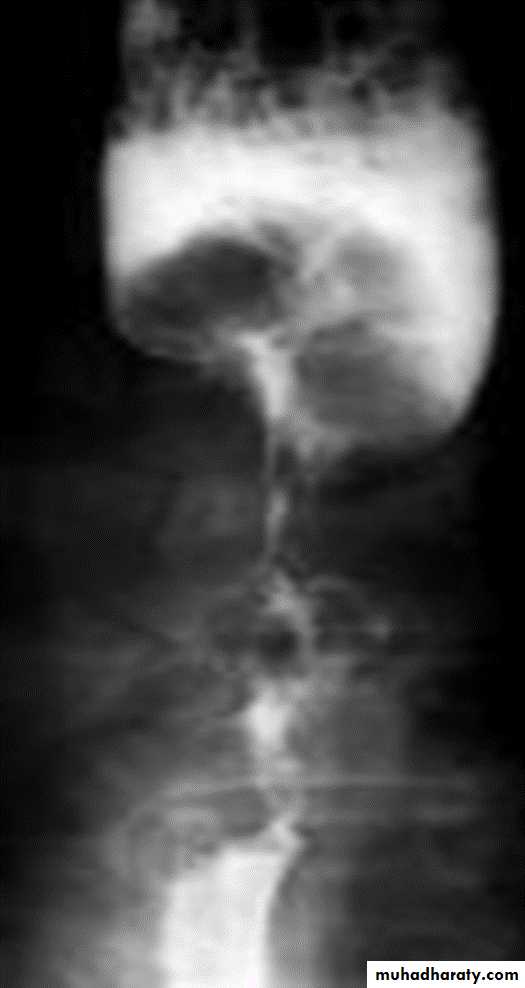

Annular Carcinoma

Narrowing :

1-Constant.

2-Irrigular .

3-Variable length.

4- Shouldering sign.

5-Fistula (double tract).

6-Soft tissue shadow of the mass